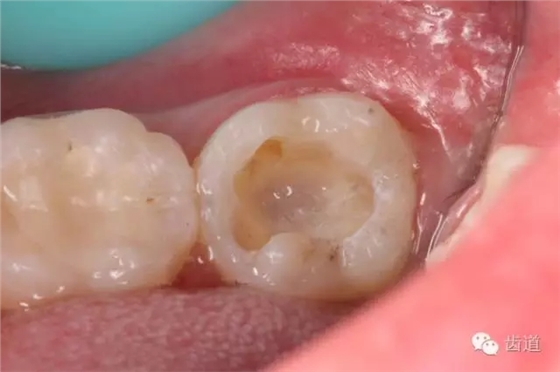

一診(2015.01.25): 主訴:左下后牙咬食疼痛約2天 既往史:無(wú)特殊 3年前因左下后牙蟲(chóng)牙不適,已在外院治療,治療后癥狀消失,約2天前,左下后牙開(kāi)始出現(xiàn)咬合時(shí)劇烈疼痛,無(wú)冷熱刺激痛,無(wú)夜間痛,否認(rèn)咀嚼硬物史,約1天前,開(kāi)始出現(xiàn)自發(fā)性跳痛,咬合可適當(dāng)緩解疼痛,未自行服用藥物,未在外院治療,癥狀持續(xù)為緩解,遂于我院就診。 口外檢查:面部對(duì)稱,無(wú)腫脹 口內(nèi)檢查: 36合面樹(shù)脂樣材料充填,邊緣密合,牙體及修復(fù)材料表面均未見(jiàn)明顯缺損及裂紋,未探及繼發(fā)齲,探痛-,叩痛-,松動(dòng)-,冷水刺激痛-,未探及牙周袋及附著喪失,牙齦無(wú)紅腫,電活力測(cè)試平均值為15;37合面樹(shù)脂樣材料充填,邊緣密合,牙體及修復(fù)材料表面均未見(jiàn)明顯裂紋,未探及繼發(fā)齲,探痛-,叩痛+++,松動(dòng)-,冷水刺激痛-,未探及牙周袋及附著喪失,牙齦無(wú)紅腫,電活力測(cè)試無(wú)反應(yīng);38埋伏阻生,可探及齦下牙冠,探痛-,牙齦無(wú)紅腫。 26、27牙體未見(jiàn)明顯充填物、缺損、齲壞及裂紋,探痛-,叩痛-,松動(dòng)-,冷水刺激痛-,未探及牙周袋及附著喪失,牙齦無(wú)紅腫; 影像學(xué)檢查: 全景片及X線根尖片顯示36合面充填物影像,靠近髓腔,未見(jiàn)根折影像,未見(jiàn)牙槽骨吸收,未見(jiàn)根分叉透射影,未見(jiàn)根尖周暗影;37合面充填物影像,靠近髓腔,未見(jiàn)根折影像,未見(jiàn)牙槽骨吸收,未見(jiàn)根分叉透射影,根管影像清晰,根中上三分之二粗大,根尖三分一分為近遠(yuǎn)中兩根管,形態(tài)均呈弧形,根尖周膜連續(xù)性中斷,根尖周透射影明顯,進(jìn)一步測(cè)量顯示:髓室頂最低點(diǎn)到髓底的距離a,與髓室頂最低點(diǎn)到根尖孔的距離b,兩者關(guān)系為a/b>0.2;38近中阻生,牙根尚未發(fā)育完全,未見(jiàn)冠周明顯透射影像;。CBCT片顯示:在水平斷層上,可見(jiàn)37根管在根尖三分之一為彎曲偏向頰側(cè)的C型,存在近遠(yuǎn)中兩個(gè)主根管,中間峽部相連;在矢狀斷層上,可見(jiàn)37根管遠(yuǎn)中根尖孔擴(kuò)大,遠(yuǎn)中根尖狹窄處位于離解剖根尖約1mm處 37慢性根尖周炎急性發(fā)作(牛牙癥) 37擬行根管治療+嵌體間接修復(fù)或根管治療+直接樹(shù)脂充填,告知患者嵌體間接修復(fù)及樹(shù)脂直接充填兩種方法的優(yōu)缺點(diǎn)、診療過(guò)程及費(fèi)用,患者知情,同意選擇根管治療+嵌體間接修復(fù)方案,簽署術(shù)前知情同意書。 37無(wú)局部麻醉下,橡皮障放置,涂布邊緣封閉劑,顯微鏡下,合面開(kāi)髓,死髓,無(wú)惡臭,無(wú)滲出液,Endo-Z開(kāi)髓鉆揭全髓頂,探及髓腔內(nèi)壞死牙髓組織,3%次氯酸鈉浸泡髓腔5min,超聲清理髓腔,顯微鏡下探及近遠(yuǎn)中主根管,及根管間峽部。通過(guò)放入初尖銼及電子根管根管長(zhǎng)度測(cè)量?jī)x確定根管長(zhǎng)度為18mm,利用手用K銼將根管預(yù)備至15#,再利用Waveone 25#預(yù)備根管至工作長(zhǎng)度,之后,10ml 3%次氯酸鈉沖洗根管,超聲無(wú)菌水蕩洗,選取25#06錐度牙膠為主牙膠,拍攝示尖片,顯示到達(dá)根管長(zhǎng)度。然后,17% EDTA凝膠處理根管壁,5ml 2%氯己定溶液完成終末沖洗,螺旋輸送器導(dǎo)入氫氧化鈣,放置棉球1,ZOE暫封。

7. 3%次氯酸鈉浸泡髓腔5min

8. 浸泡后超聲清理髓腔,去除髓腔內(nèi)殘留牙髓組織

9. 預(yù)彎初尖銼探入根管